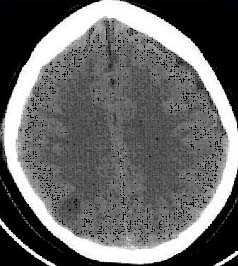

Применение компьютерной томографии в нейротравматологии существенно изменило представление о возможностях диагностики различных черепно-мозговых повреждений. КТ является в настоящий момент «золотым стандартом» - наиболее информативным методом обследования больных с черепно-мозговыми травмами и позволяет в самые короткие сроки судить о механизмах возникновения поражения мозга, его характере, распространенности, выраженности отека и дислокации мозга, а также динамике этих изменений.

- выявить наличие внутричерепной гематомы (её характер, локализацию, размеры),

- выявить наличие очага ушиба головного мозга (его локализацию, размеры, характер, наличие геморрагического компонента),

- выявить субарахноидальное кровоизлияние,